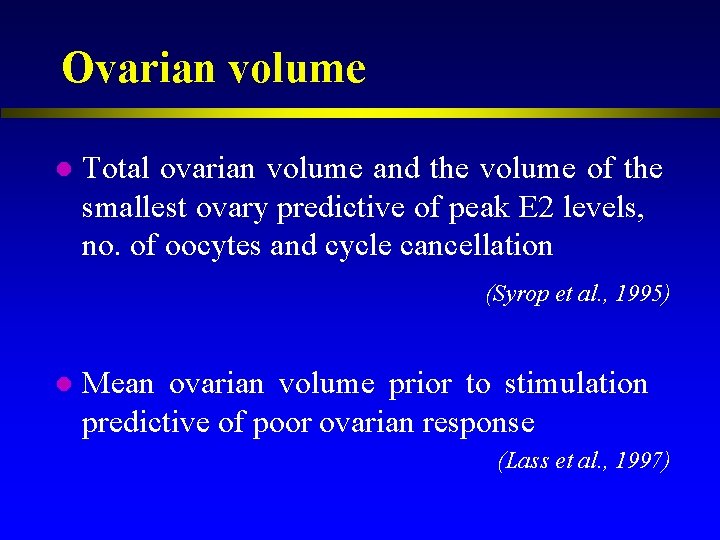

Ovarian volume

Ovarian volume l Total ovarian volume and the volume of the smallest ovary predictive of peak E 2 levels, no. of oocytes and cycle cancellation (Syrop et al. , 1995) l Mean ovarian volume prior to stimulation predictive of poor ovarian response (Lass et al. , 1997)